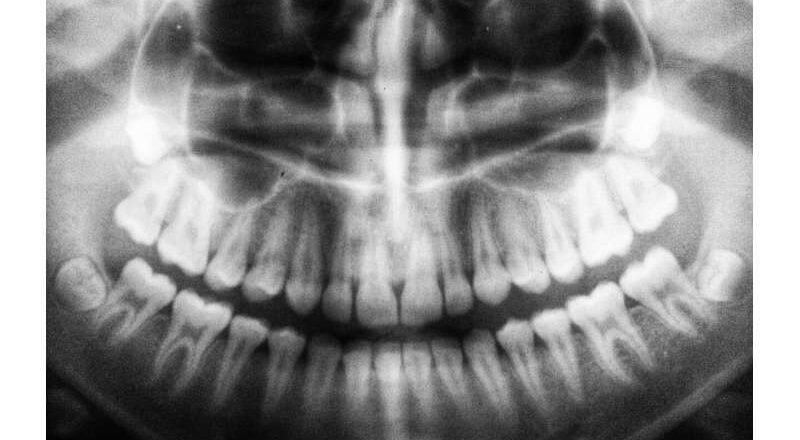

Como dentista e investigador de salud pública, durante años observé el mismo patrón. Los pacientes con infecciones profundas de la raíz a menudo presentaban problemas de salud más graves, especialmente aquellos con diabetes. Todavía no entendía por qué. Ahora, estudios científicos están empezando a explicar la relación: tratar una infección dental profunda también puede ayudar al cuerpo a controlar el azúcar en sangre.

Una infección dental puede parecer un problema de salud relativamente leve, pero sus efectos pueden extenderse mucho más allá de la boca. Investigaciones recientes han demostrado que las personas que se sometieron a un tratamiento de conducto para infecciones persistentes en la punta de la raíz experimentaron nivele...